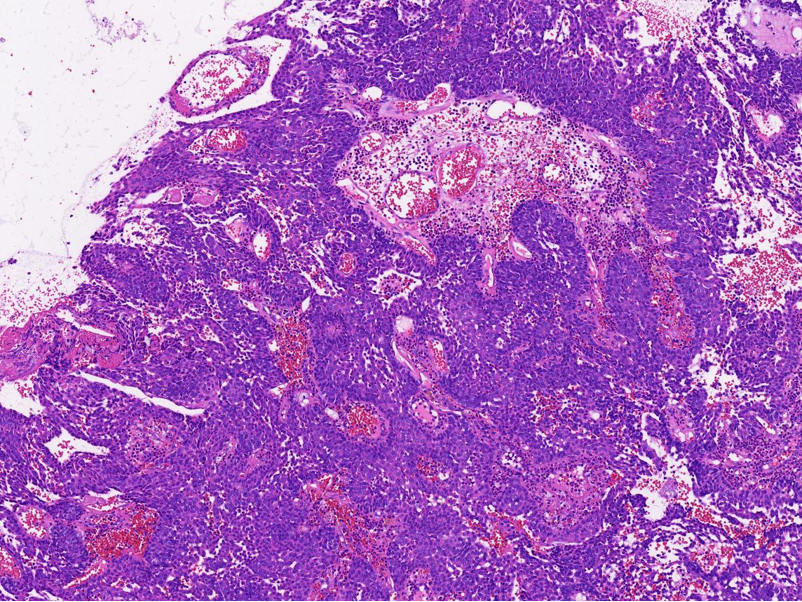

病理特征:宽薄乳头、 迷宫样内翻生长、单一肿瘤细胞形态、棘层松解、显著中性粒细胞浸润;

可见:细胞旋涡、透明细胞变、微囊形成、黏液纤毛上皮帽、部分肿瘤细胞异型性增加、坏死。

具有纤毛上皮帽